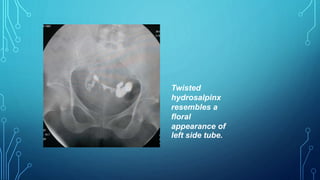

Twisted

hydrosalpinx

resembles a

floral

appearance of

left side tube.